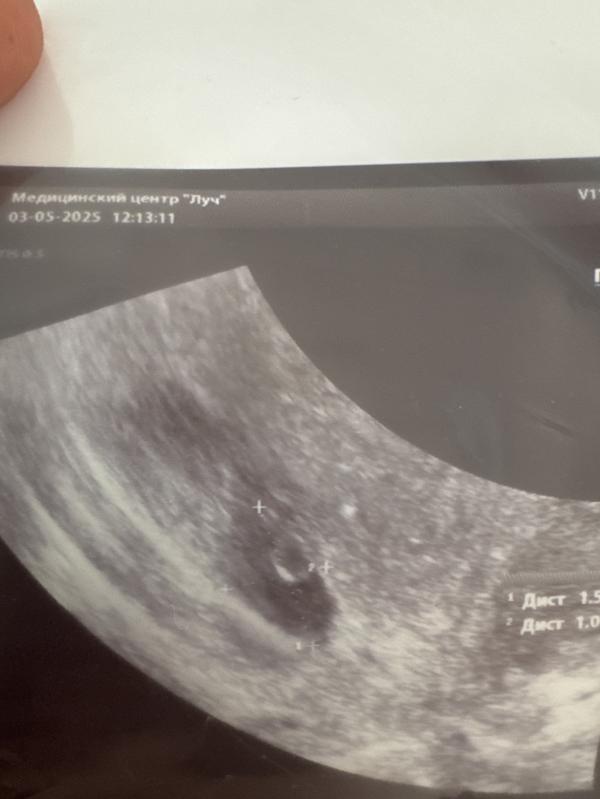

Срок ровно 7 недель. Легла.

Узистка: вижу плодное яйцо, желточный мешочек… эмбрион не вижу. Вот он тут должен быть. Ну не паникуйте такое бывает.

Ищет. Показывает эмбрион с сердечком немножко удалось послушать. Ктр 6,8 мм.

Теперь думаю, почему не указали размер жм - вдруг он большой и это плохо

Эмбрион соответствует сроку, если это верные данные 0,68 мм и сердцебиение есть. Но боже … я теперь так боюсь